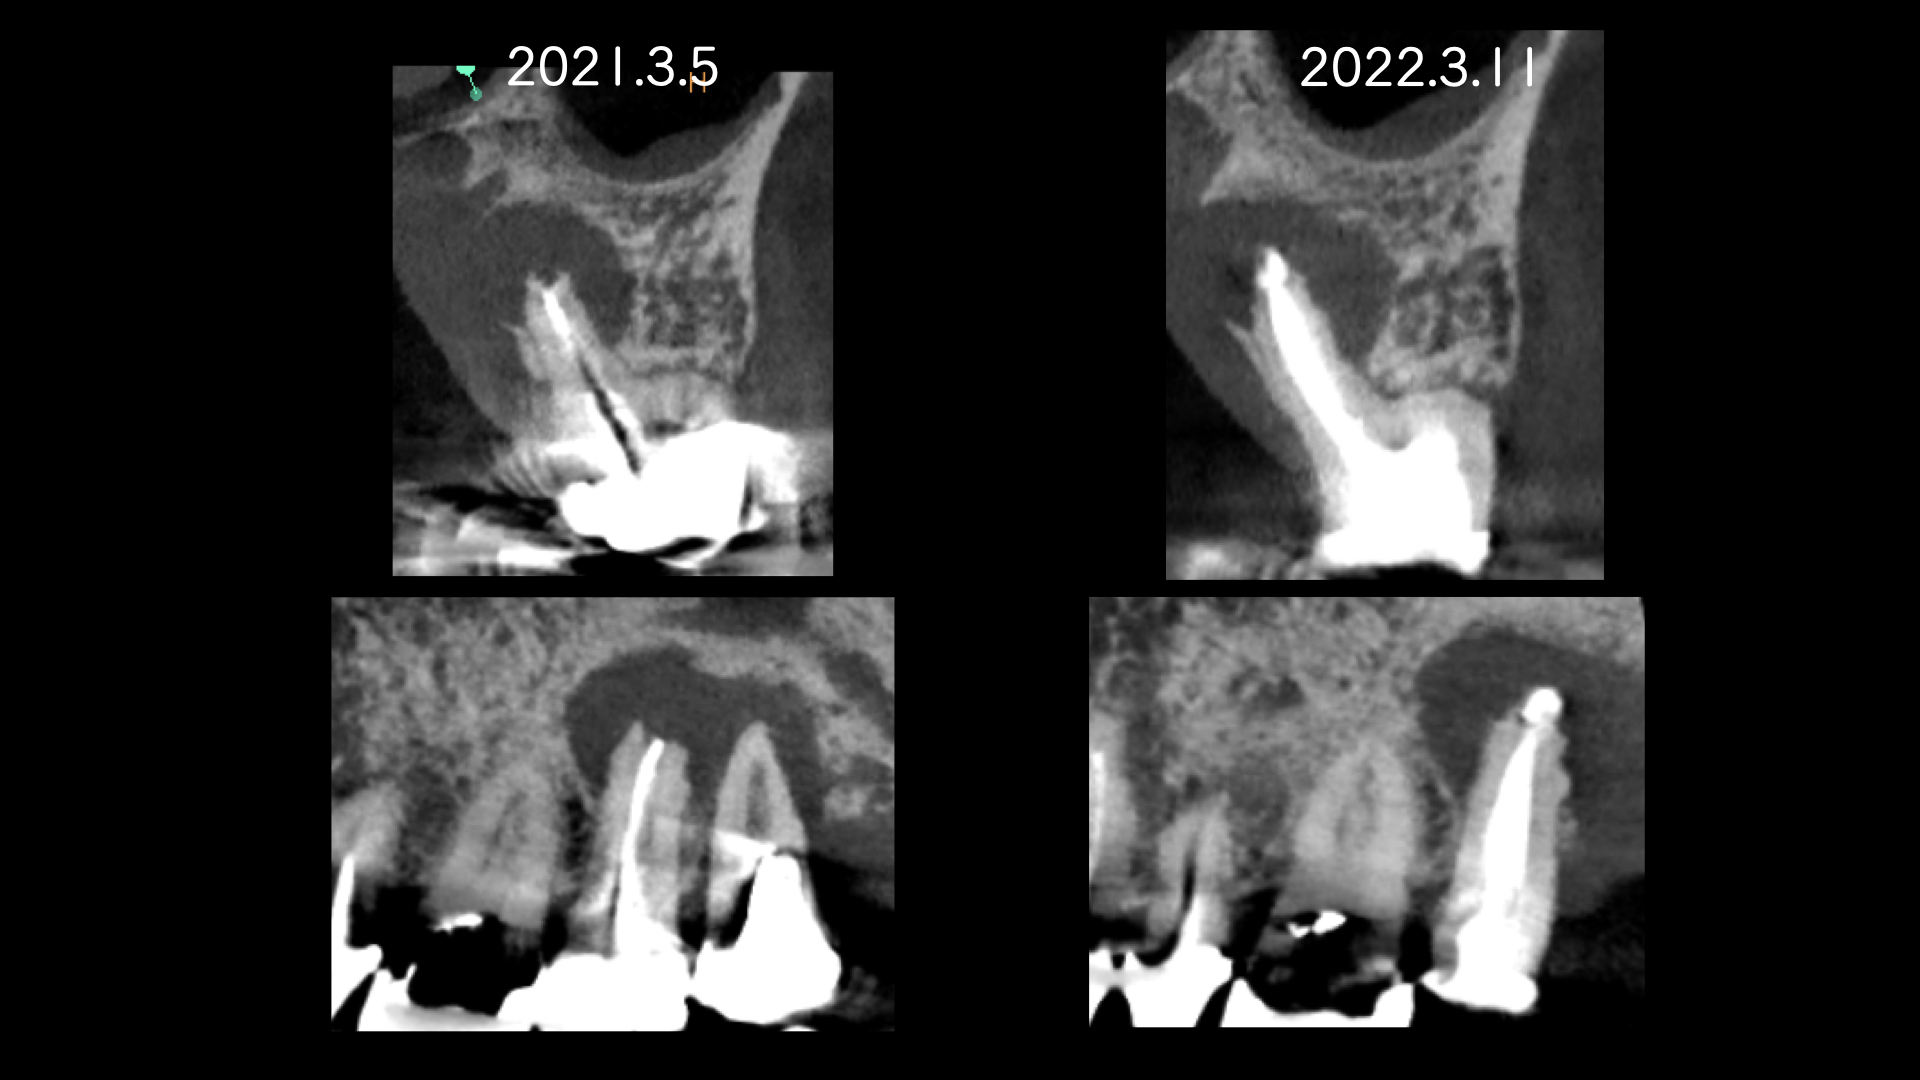

右の画像のCT上で根尖部にかなり大きな透過像があります。

噛み合わせの反対側(下顎)はインプラント治療をおこなっており、経過をみていましたが全く変化がありませんでした。

患者さんの都合もあり1年後に歯根端切除(外科的歯内療法)をおこなうことになりました。

教科書によると、この部位は適応症でなく、一般的には意図的再植の適応症にはなりますが、このような歯根が離開している歯を一度抜歯するのは破折のリスクがあります。

適応症ではないのは大口蓋動脈の存在です。

論文より今回のケースは安全であると判断し、歯根端切除で対応しました。